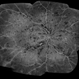

- peripheral ischemia

- Imaging device

- Fundus camera

- Peripheral ischemia by angiography with montage